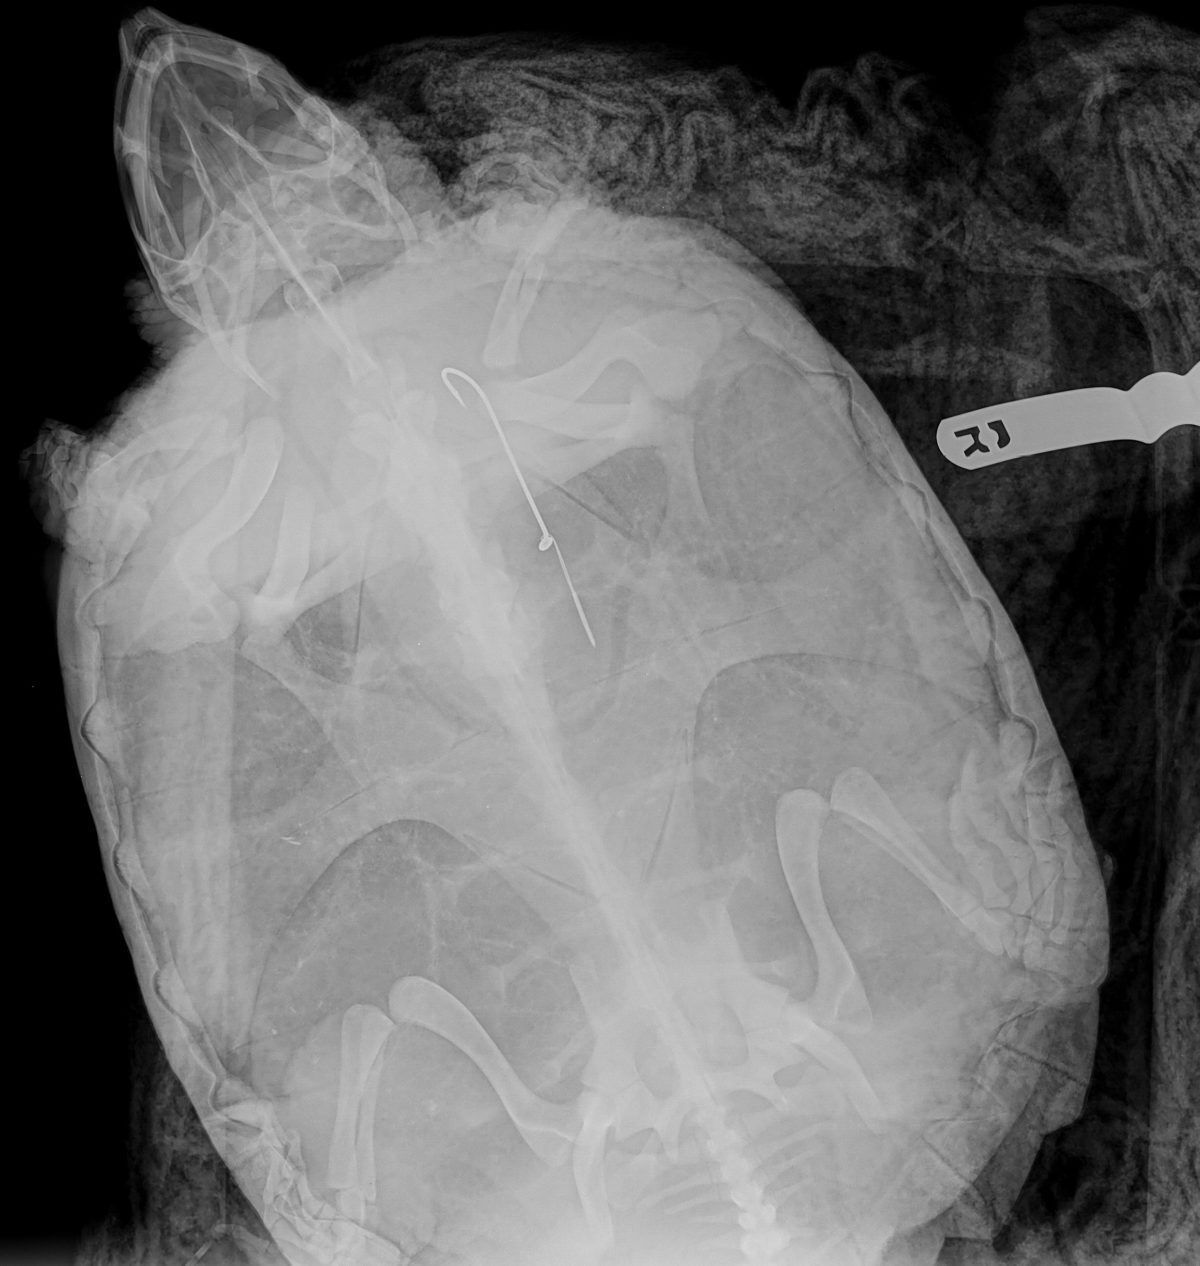

Snapping Turtle with a lure in its body Photo courtesy of Toronto Wildlife Centre

It’s not alway easy to tell if an animal is suffering from an injury caused by a hook. Even if you can’t see any fishing gear, if an animal is behaving oddly or reacting slowly that’s a sign that something’s wrong. Karvonen recounts the recent admittance of a snapping turtle that was brought to the centre because it was sitting lethargically in a parking lot. Once an x-ray was taken of the turtle, staff were able to see a fishing hook deep in the turtle’s esophagus. After a trip to the emergency clinic for a difficult surgery, the hook was removed and the snapping turtle released.